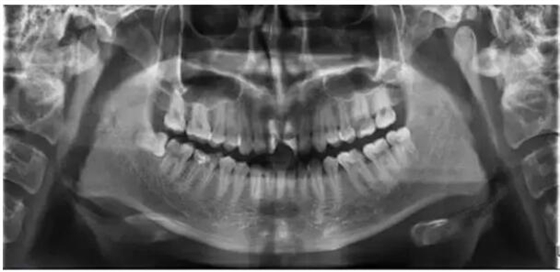

通過全面詢問病史,臨床檢查和拍攝X光片,結(jié)合患者的主觀癥狀、身心狀態(tài),擬定治療方案,充分進(jìn)行醫(yī)患交流并詳細(xì)記錄。

四、確認(rèn)根管工作長度

應(yīng)用平行投照X線方法、根管長度測(cè)量儀確定根管長度 ,最好的辦法是:技術(shù)+經(jīng)驗(yàn)+根管長度測(cè)量儀+ X線 。